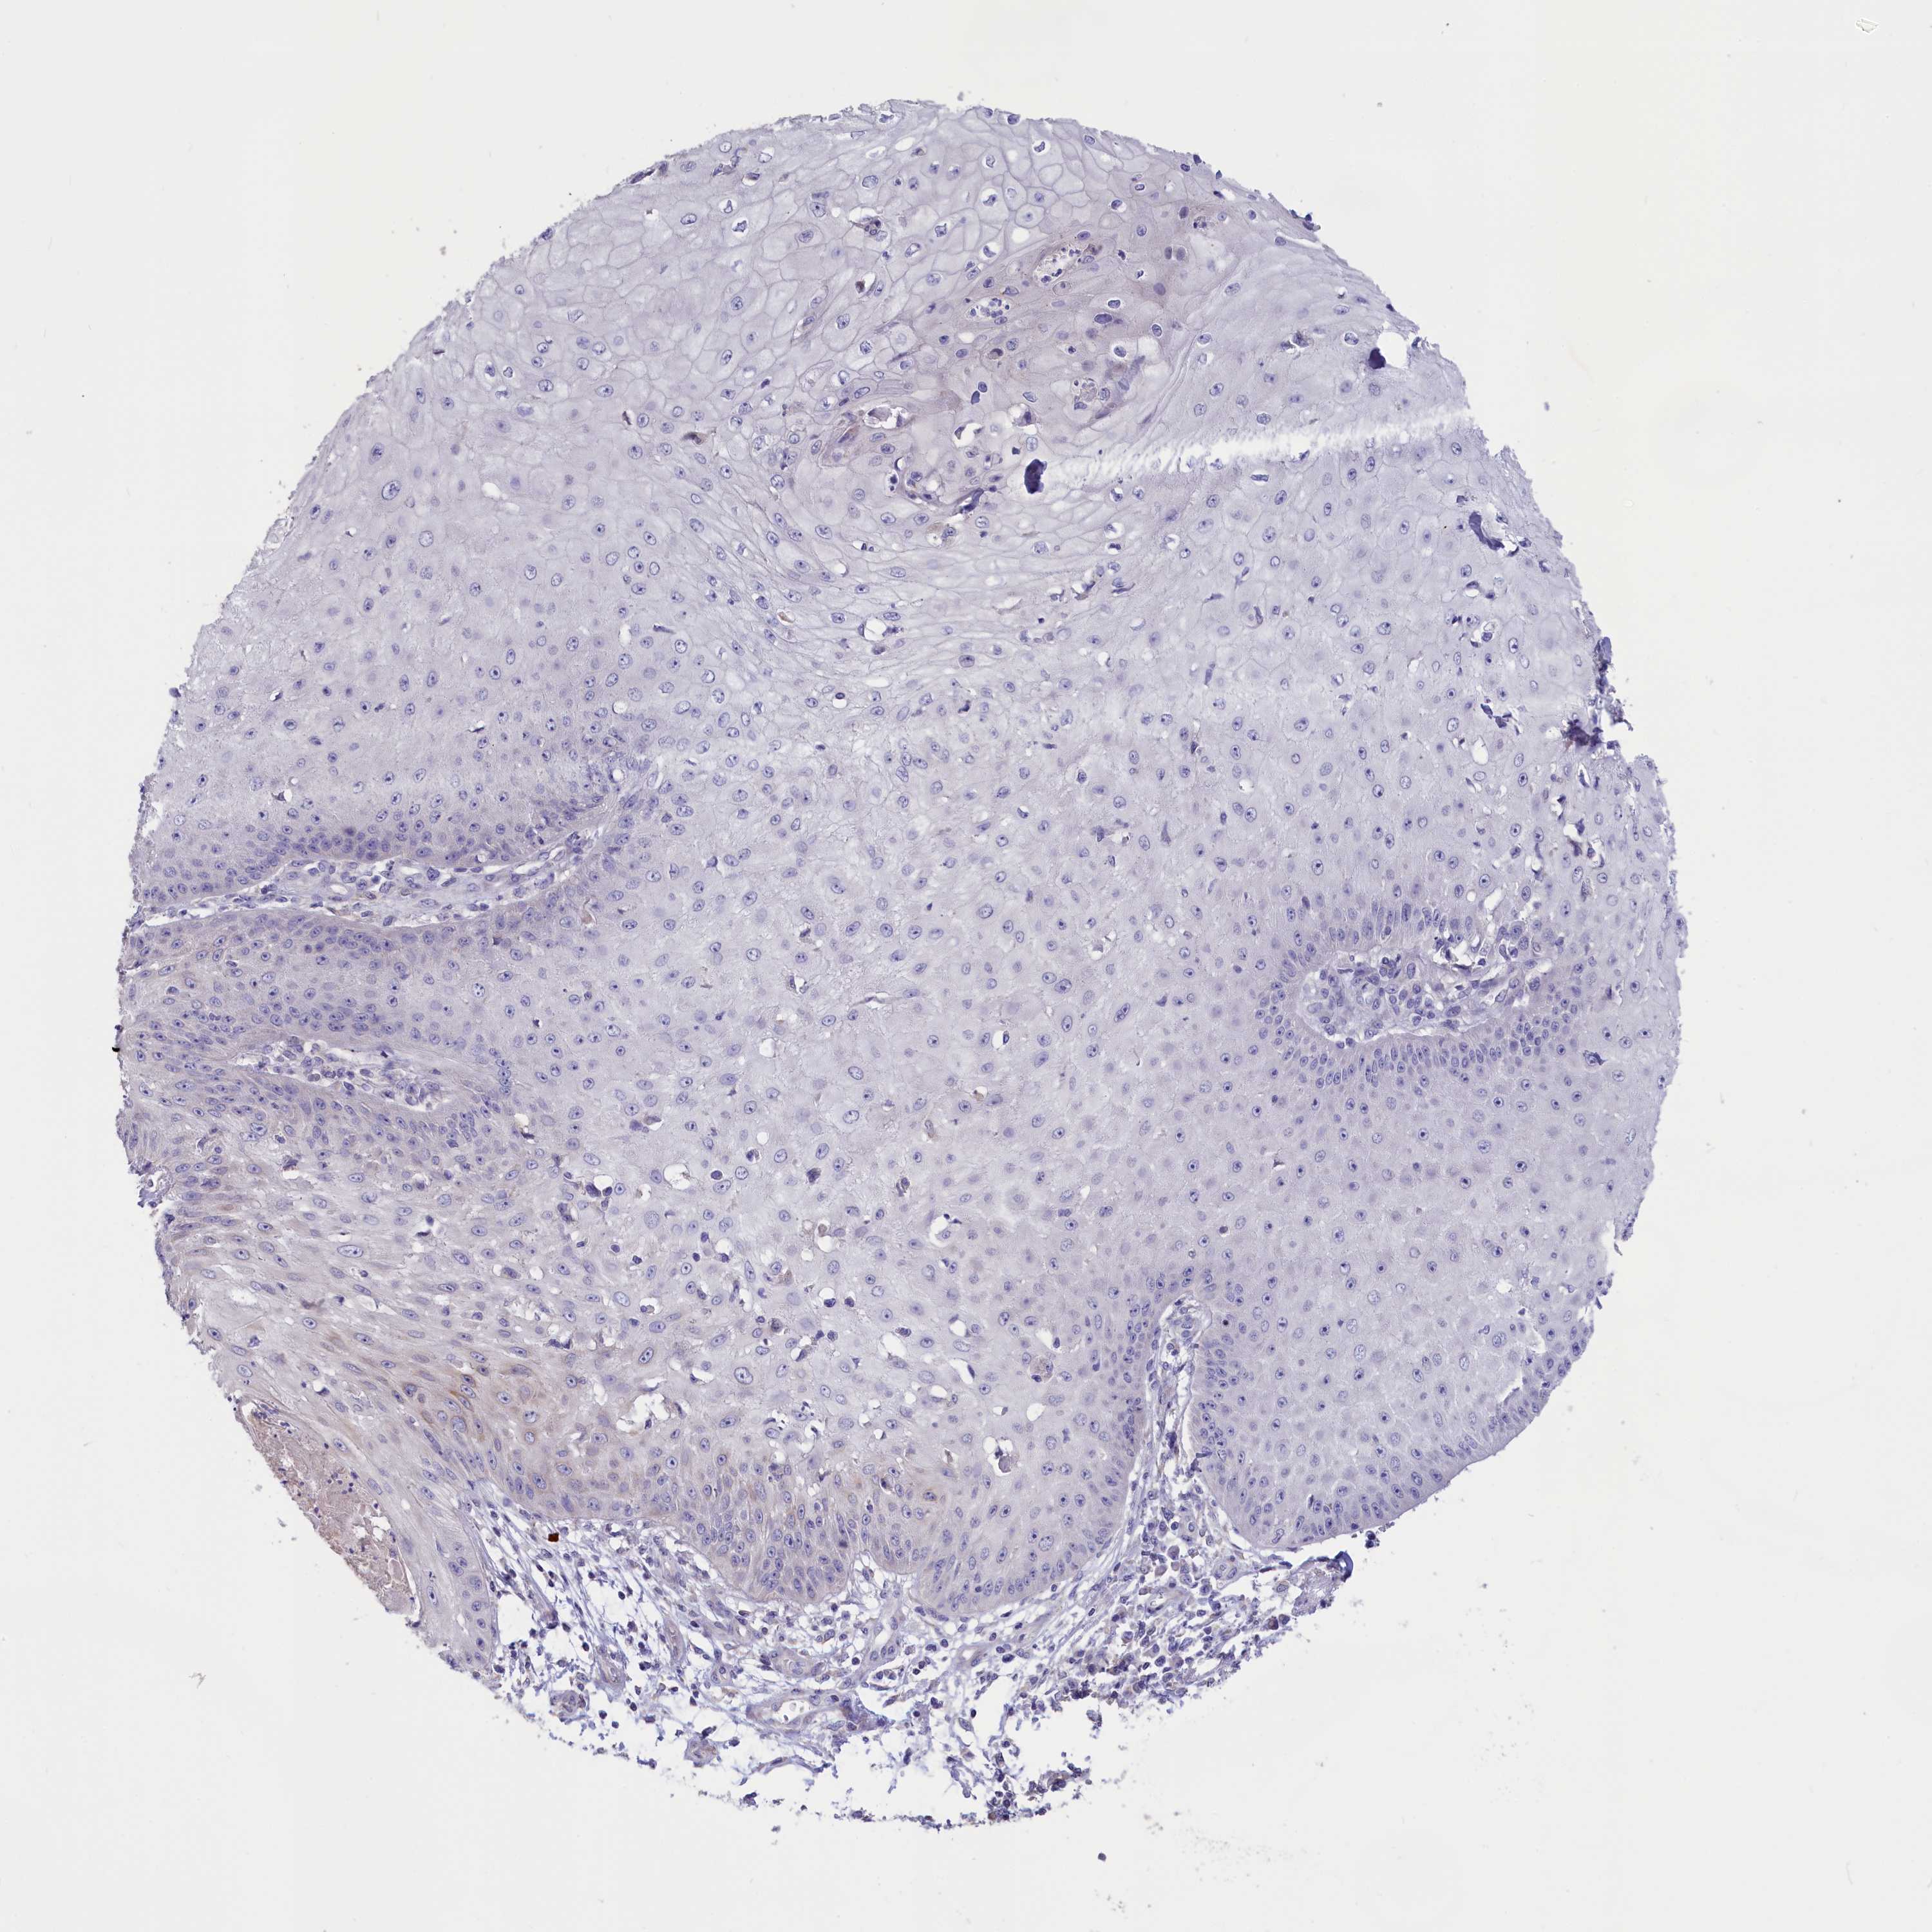

SKIN CANCER - Protein expressioni

A mouse-over function shows sample information and annotation data. Click on an image to view it in a full screen mode. Samples can be filtered based on level of antibody staining by selecting one or several of the following categories: high, medium, low and not detected. The assay and annotation is described here.

Each image is clickable and will lead to virtual microscopy that enables deeper exploration of all samples and also displays staining intensity scores, fraction scores and subcellular localization as well as patient and tissue information for each sample.

Antibody HPA041622

Not detected

Negative

None

Squamous cell carcinoma in situ, NOS